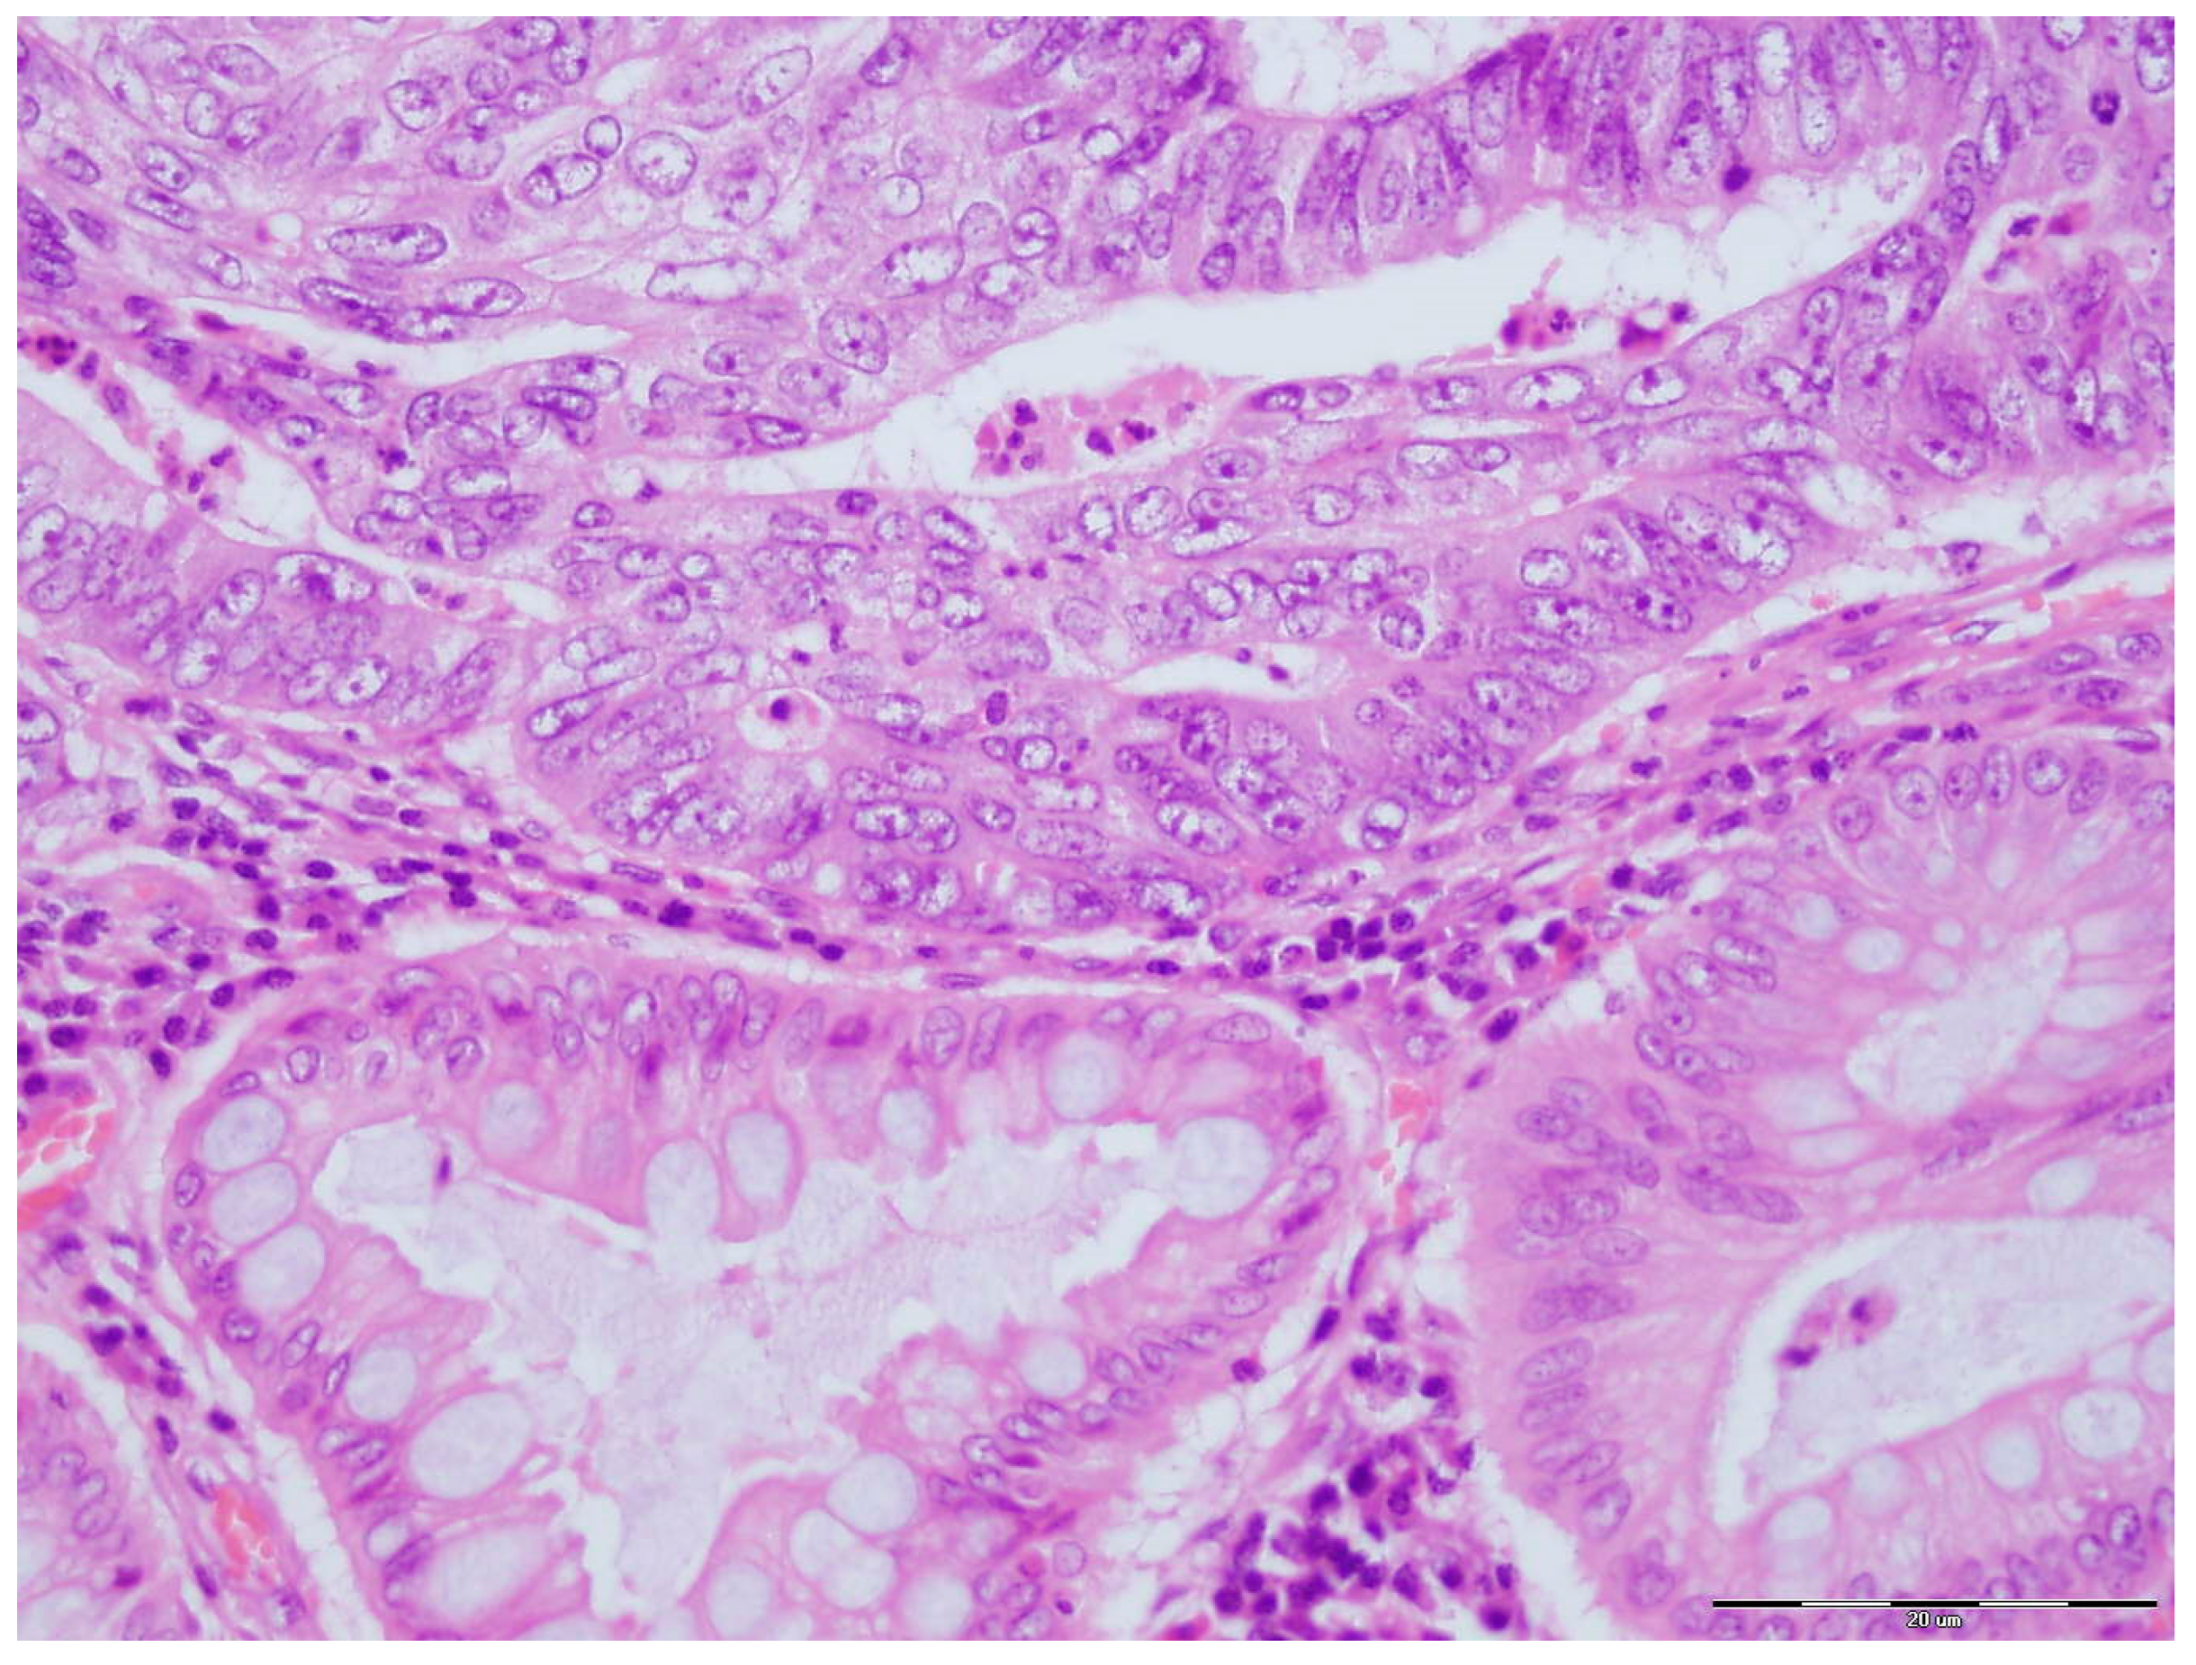

2.3. PLK-1 Immunohistochemistry